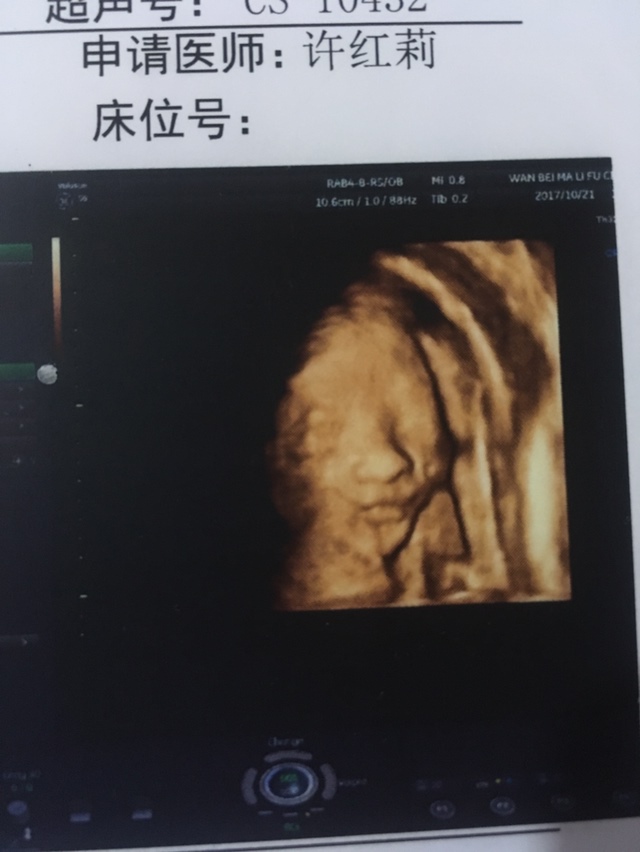

看图片,宝宝长相挺漂亮的。

孕26周+6天